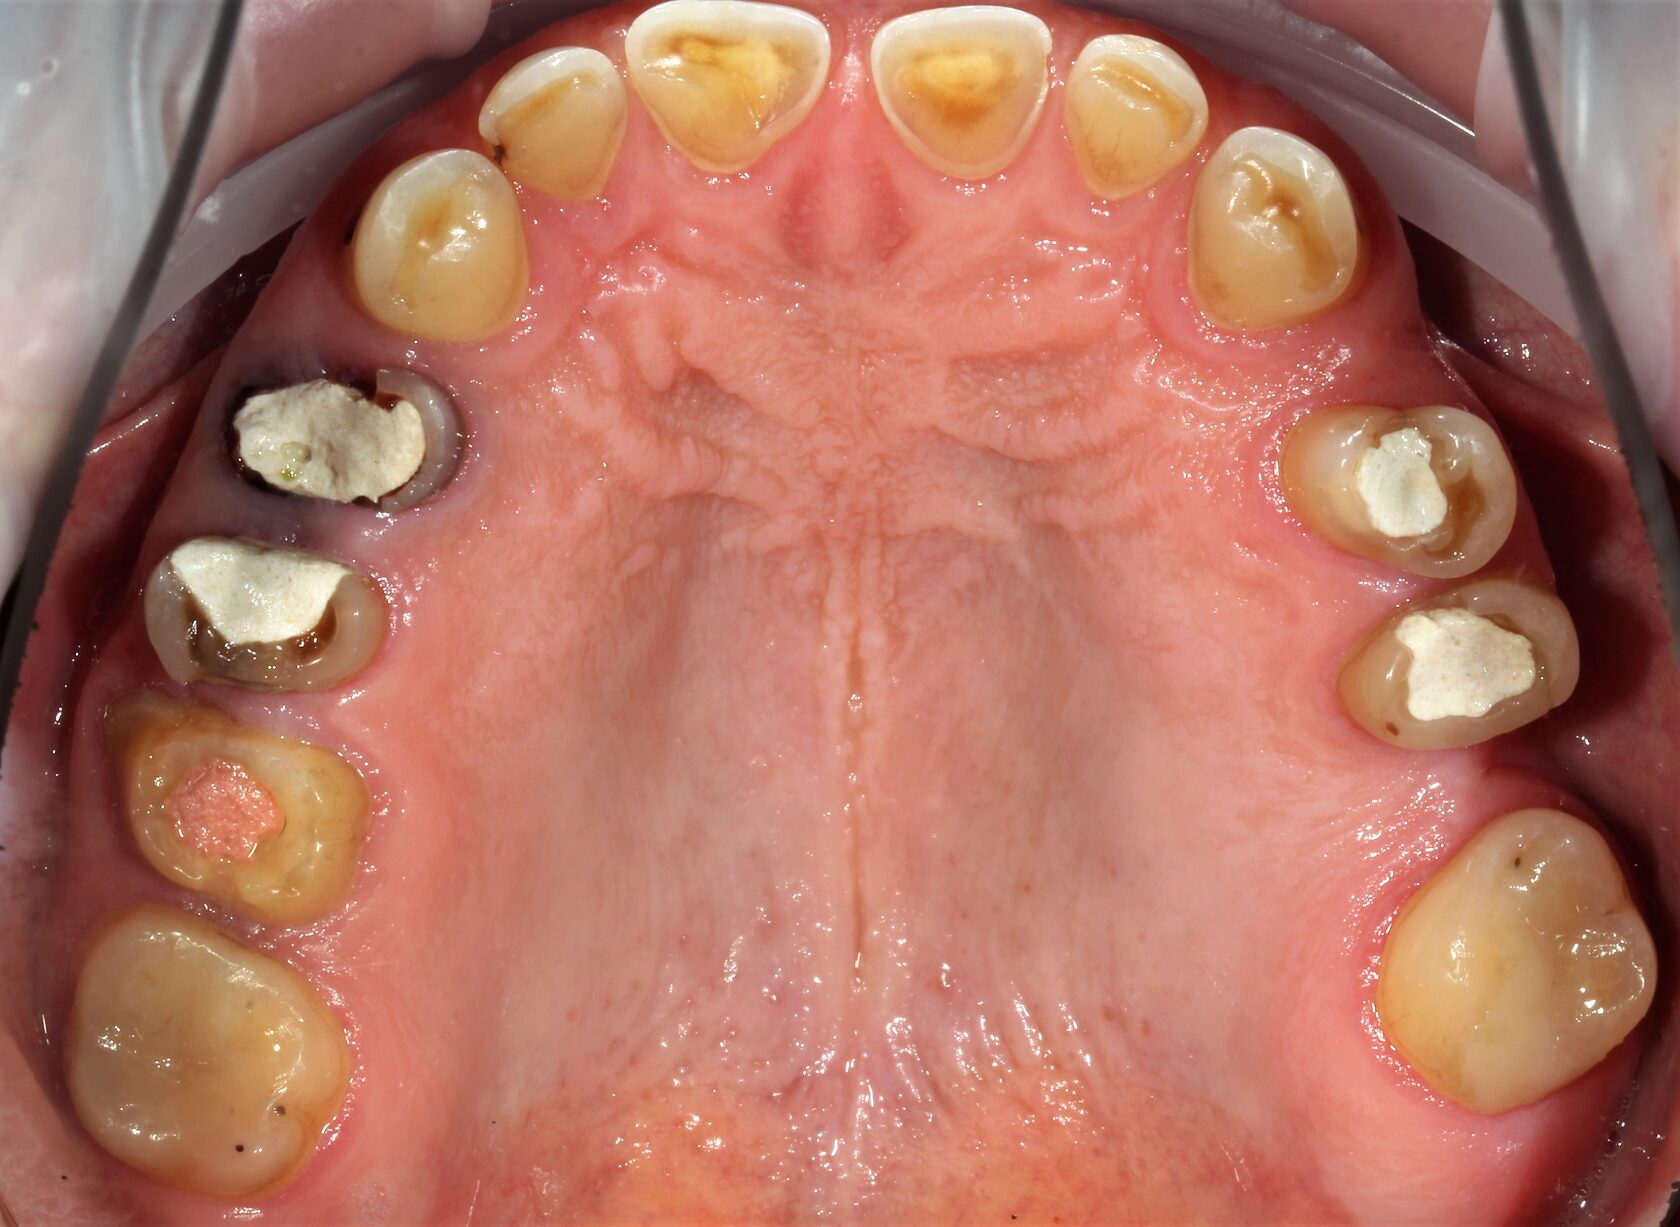

В данном клиническом случае представлена комплексная работа, состоящая из:

1 Терапевтический этап - лечение кариеса, подготовка корневых каналов и восстановление

культей зубов для установки коронок.

2 Хирургчий этап - удаление 2-х зубов с одномоментной дентальной имплантацией.

3 Сложное функционально-эстетическое протезирование (завышение прикуса на временных

коронках, стабилизация мышечного тонуса и позиции ВНЧС, перевод временных конструкций

в постоянные).

Длительность лечения составила более 1 год.